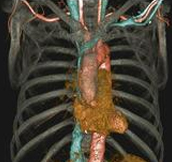

Body angiography with automatic bone and table removal - MIP reconstruction. Case: Aortic dissection. Left common iliac artery occlusion. Scanning: P0.83, 0.5s, 360mA, 100kV, weight 80kg, contrast 80cc

Body angiography with automatic table removal ? colored volume rendering reconstruction. Case: Aortic dissection. Left common iliac artery occlusion. Scanning: P0.83, 0.5s, 360mA, 100kV, weight 80kg, contrast 80cc